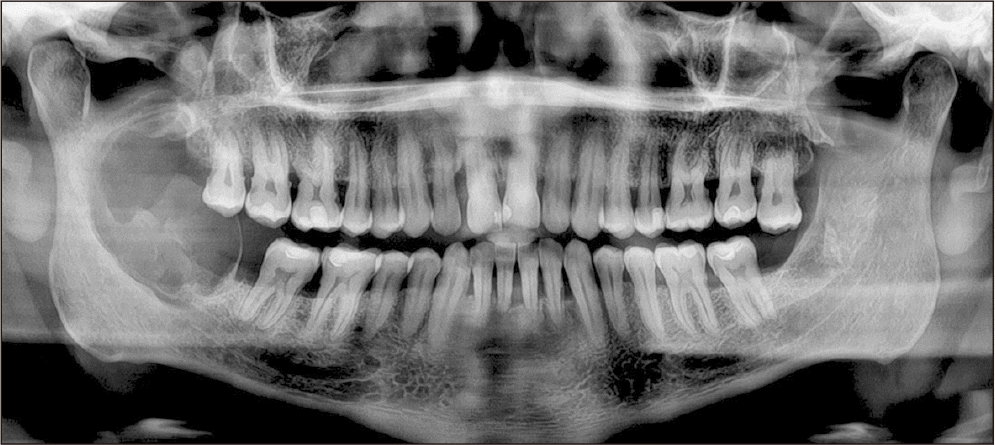

A 54-year-old female patient with a medical history of asthma and arterial hypertension, under treatment with prednisone, vitamin D, losartan, and primaquine. She had quit smoking 20 years prior. She was admitted to the maxillofacial surgery service due to an asymptomatic swelling in the mandibular region of the left body and angle, associated with teeth 3.6 and 3.7, which were displaced and mobile. Panoramic radiography revealed a multilocular radiolucent lesion expanding the cortical bone, with an approximate diameter of 8 cm.(Fig. 1) Biopsy confirmed the diagnosis of glandular odontogenic cyst. Surgery under general anesthesia was planned: excision of the lesion with a safety margin, reconstruction with an osteosynthesis system (OTS), and placement of an acrylic spacer to later evaluate the presence or absence of recurrence and to resolve the definitive reconstruction of the bone defect at a later stage.(Fig. 2)

Fig. 1

Preoperative panorama X-ray: multilocular radiolucent lesion in the region of the left mandibular body and angle.